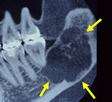

顎骨腫瘍

下顎の中に腫瘍ができ、骨を溶かしています(黄色の矢印)。